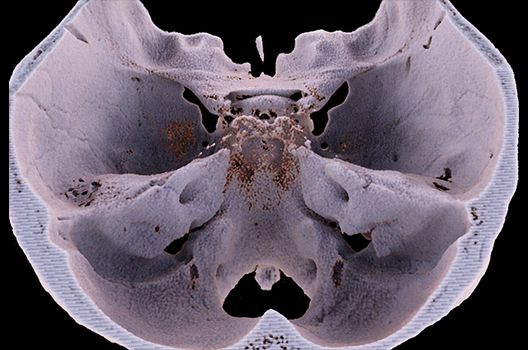

Die Schwerpunkte in der CT-Forschung liegen in der Bildnachverarbeitung, der Dosis- und Artefaktreduktion sowie der quantitativen und automatisierten CT-Bildanalyse.

Die Computertomographie (CT) ist ein Verfahren, bei der mit Hilfe von Röntgenstrahlung Schnittbilder des Körperinneren angefertigt werden. Unser Bestreben ist es hierbei, bei möglichst niedriger Strahlendosis eine bestmögliche Bildqualität zu erzielen. Eine zunehmend große Rolle in der radiologischen Forschung spielen zudem die Automatisierung in der Bildanalyse und die computergestützte Auswertung großer Datenmengen, wie sie bei einer CT-Untersuchung anfallen. Wir arbeiten in enger Kooperation mit den Geräteherstellern zusammen und sind daher maßgeblich an der Entwicklung und Erprobung neuer Techniken beteiligt.